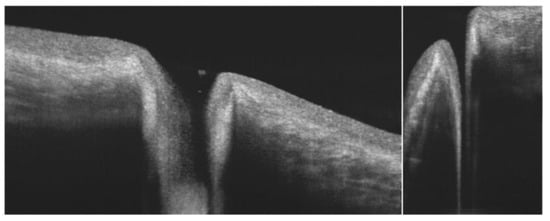

6.3. Meibomian Glands